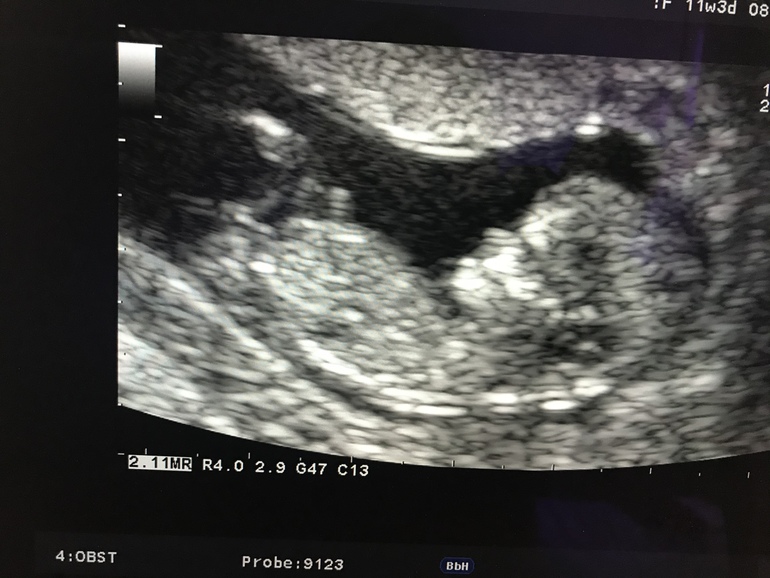

Первый скрининг. 11.3 акушерские

Врач сказала что все хорошо , все по сроку. Носик длинный и красивый , но написано что носовая кость не визуализируется, вот это все же чуть беспокоит. Сказала что с большой вероятностью девочка , что видно очень хорошо девчонку , шустрая , красивая 😱😍😍😍

вот как тут можно увидеть что девочка??? Кто тоже понимает ? Или на этом снимке не видно

По половому бугорку определяют: у мальчиков торчит больше, у девочек более сглажен. На Вашем снимке, если честно, мне не видно)) Может, кто поглазастее увидит)))

Думаю видно) недавно тоже была на узи, тоже точно девочка сказали так как видно две полосочки там-то точно девочка !!))и у вас я вижу полосочки такие как мне показывали)

Они смотрят на угол между писькой и позвоночником. Прочитайте в интернете об этом. Там даже фото мальчика и девочки. И разница видна. Но не факт что вы увидите. Врач есть врач.